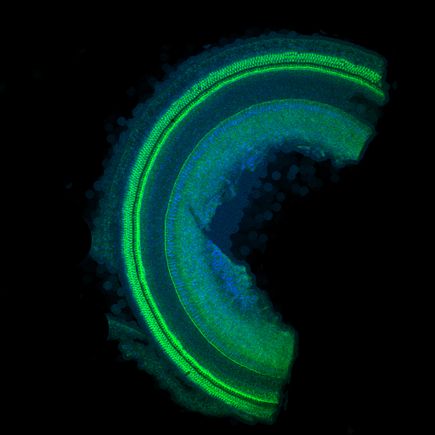

Seeking to stem the tide of permanent hearing loss from the use of lifesaving antibiotics, researchers at Oregon Health & Science University have found that patients stricken with dangerous bacterial infections are at greater risk of hearing loss than previously recognized. Inflammation from the bacterial infections substantially increased susceptibility to hearing impairment by increasing the uptake of aminoglycoside antibiotics into the inner ear, the researchers report. Their findings are published in online in the journal Science-Translational Medicine.

Aminoglycosides, antimicrobials that are indispensable to treating life-threatening bacterial infections, are toxic to the ear. Relied on by physicians to treat meningitis, bacteremia and respiratory infections in cystic fibrosis, aminoglycosides kill the sensory cells in the inner ear that detect sound and motion.

When Steyger and colleagues gave healthy mice a low amount of aminoglycoside, the rodents experienced a small degree of hearing loss. If the mice had an inflammation that is typical of the infections treated with aminoglycosides in humans, the mice experienced a vastly greater degree of hearing loss.